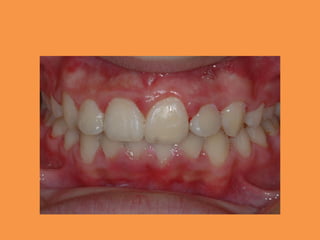

Figure 1: Intraoral view showing the

absence of 11

Figure 1: Intraoralview showing the absence of 11